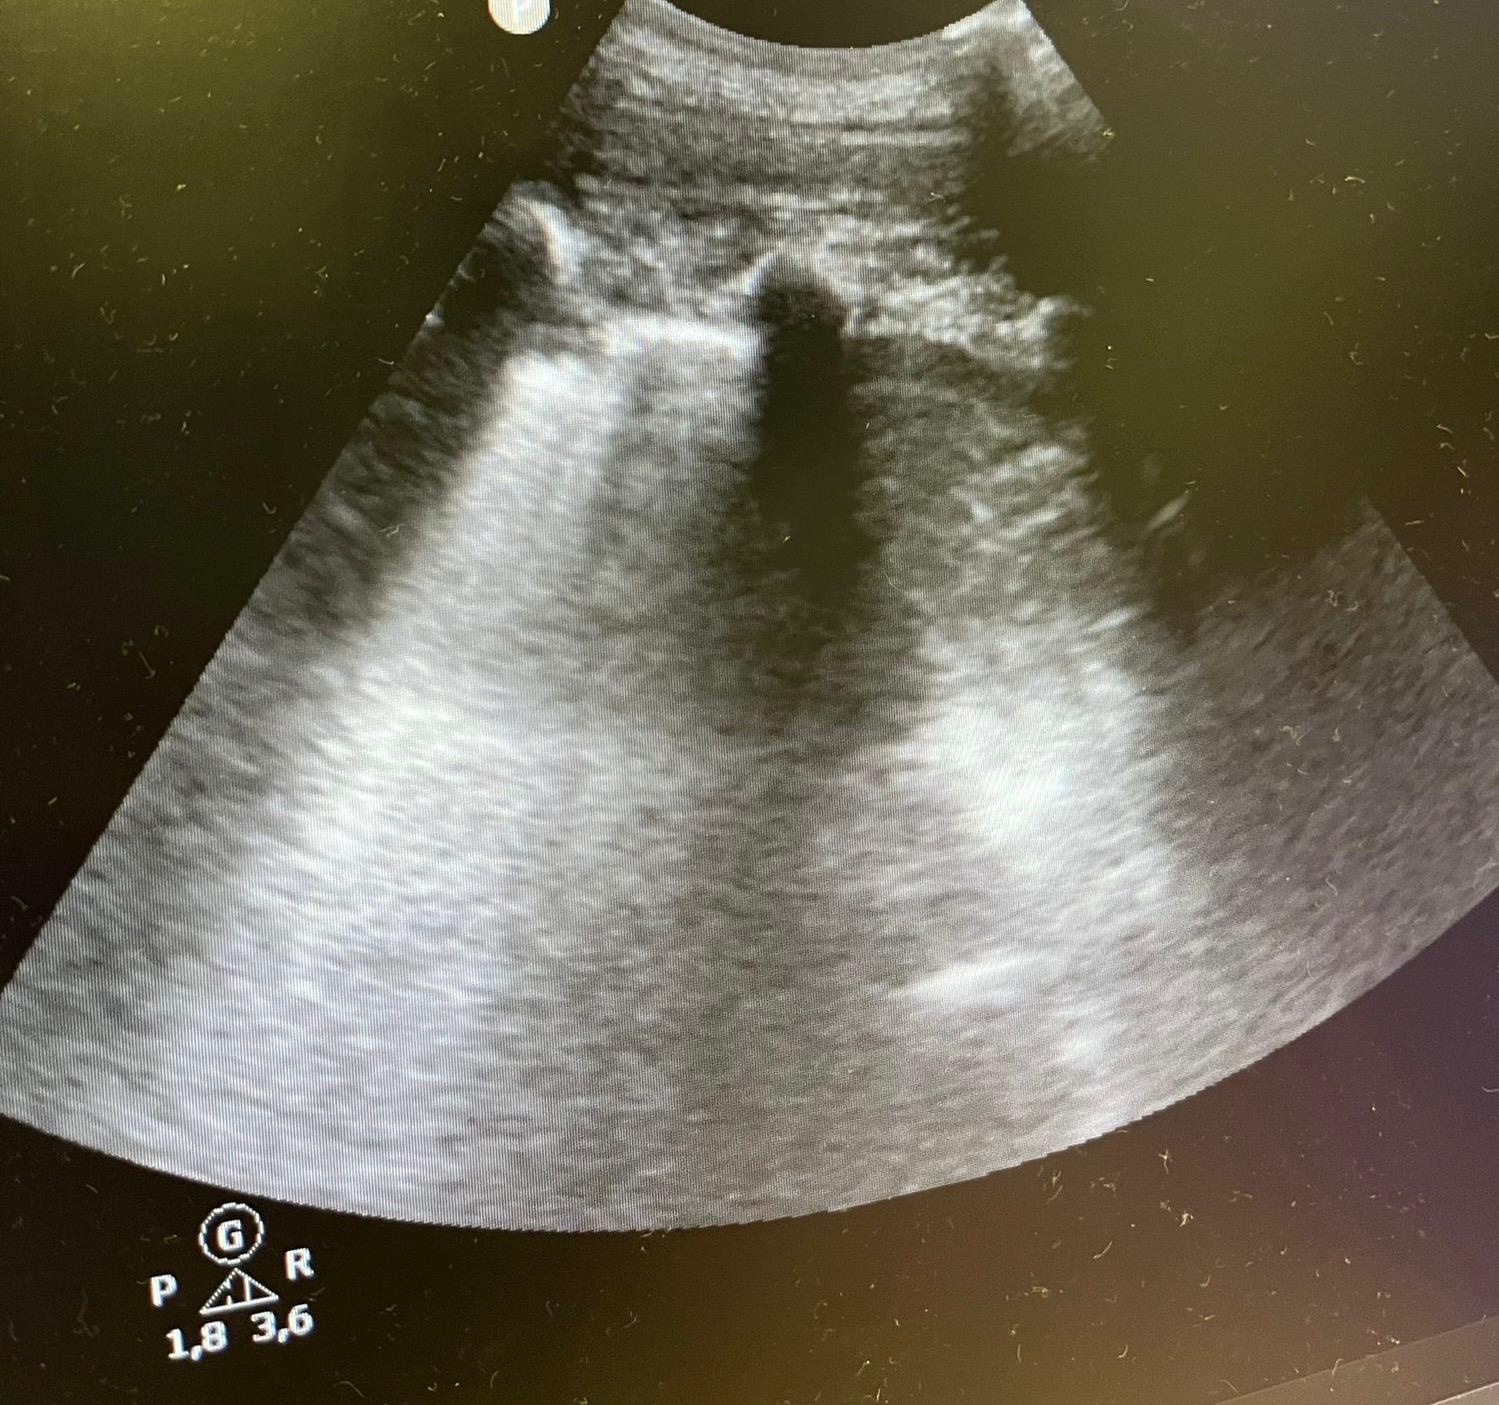

Juicio clínico: Se orienta como neumonía ya que el paciente cursa con fiebre y tiene una ecografía compatible; dado buen estado general del paciente y escalas FINE 35, CURB 65 de 0 se decide alta a domicilio con tratamiento oral.

En este caso podemos contemplar que nos es muy útil tanto en consultas de Atención Primaria como en Urgencias el uso de la ecografía como herramienta cuando tenemos dudas diagnósticas. El signo de la medusa es una imagen dinámica de la ecografía que se puede producir en caso de derrame pleural por una atelectasia compresiva, vemos una imagen similar a la de un brazo de medusa flotando en el contenido líquido. Conocer este signo puede ser de utilidad para sospechar un derrame pleural.